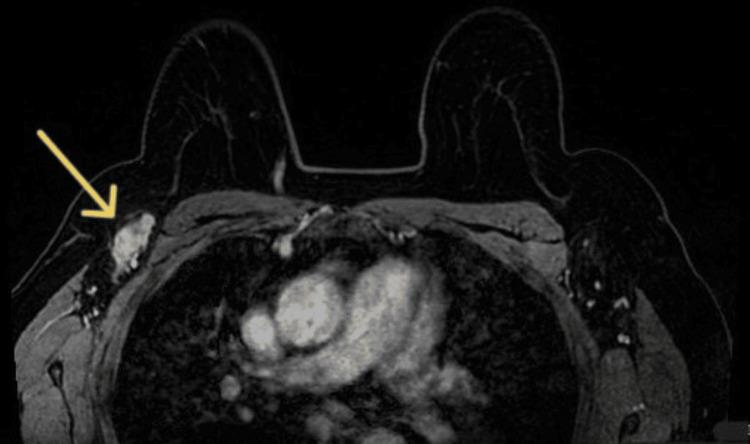

Breast cancer exhibits a high prevalence among women and represents a significant contributor to cancer-related mortality. Routine screening substantially reduces mortality rates by enabling the early detection of tumors. This report describes an uncommon case of breast cancer located deep near the intermammary groove in a 63-year-old woman. The tumor's asymptomatic presentation, small size, and atypical location posed a diagnostic challenge. However, screening mammography revealed a suspicious axillary adenopathy, prompting further evaluation. MRI identified a 6 mm intermammary groove-adjacent lesion, and a biopsy confirmed the cancer diagnosis. Staging excluded metastasis. The patient underwent neoadjuvant chemotherapy, and nearly a year later, MRI imaging showed total remission. Sentinel lymph node biopsy was negative for breast cancer, suggesting a favorable prognosis. This case highlights the importance of primary care, promoting screening programs, and early detection in improving prognosis. Enhanced access to screening and meticulous radiological interpretation are critical to optimizing patient outcomes.

乳腺癌在女性中具有很高的发病率,是癌症相关死亡率的重要促成因素。常规筛查通过早期发现肿瘤,大幅降低了死亡率。本报告描述了一例罕见的乳腺癌病例,该病例发生在一名63岁女性乳房间沟深处。肿瘤无症状、体积小且位置不典型,给诊断带来了挑战。然而,乳腺钼靶筛查发现可疑的腋窝淋巴结肿大,促使进一步评估。磁共振成像(MRI)发现一个与乳房间沟相邻的6毫米病变,活检确诊为癌症。分期检查排除了转移。患者接受了新辅助化疗,近一年后,MRI成像显示完全缓解。前哨淋巴结活检结果为乳腺癌阴性,提示预后良好。该病例突出了初级保健、推广筛查项目以及早期发现对改善预后的重要性。加强筛查途径和细致的影像学解读对于优化患者治疗效果至关重要。